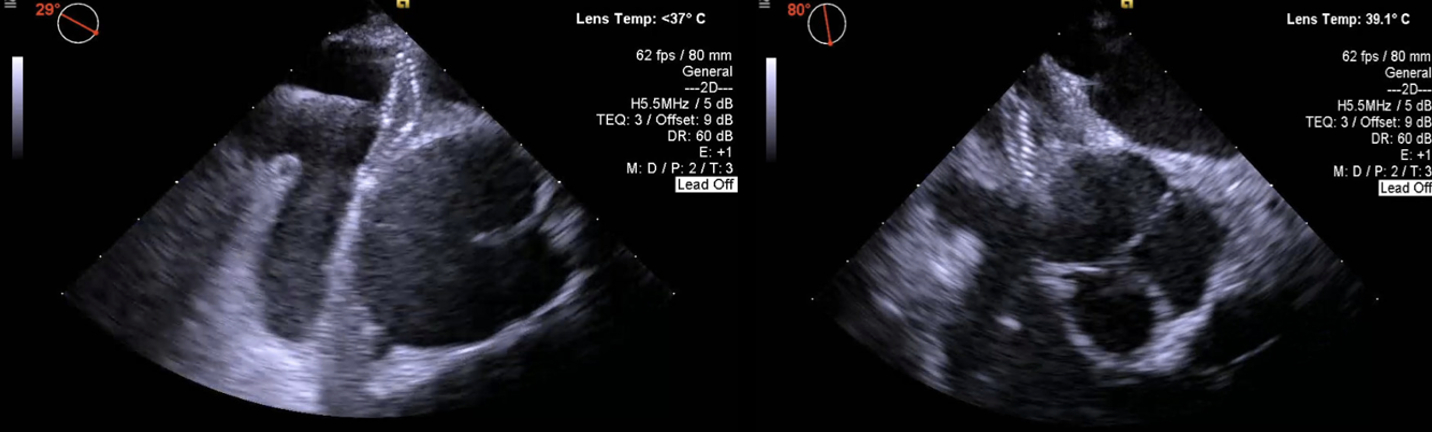

A 78-year-old man with a history of Parkinson’s, TIAs, and scoliosis presented with a sequalae of symptoms concerning for recurrent TIA, however extensive workup demonstrated no evidence of acute intracranial abnormalities. Subsequently, he developed acute hypoxic respiratory failure requiring high-flow nasal cannula. Initial chest CT angiography (CTA) and X-ray were negative for acute pulmonary pathology. A transthoracic echocardiogram (TTE) with bubble study was positive for moderate right-to-left shunt through a patent foramen ovale (PFO). Subsequent imaging modalities, including right heart catheterization, transesophageal echocardiography (TEE) with bubble study, cardiac CT, and cardiac MRI, exhibited normal hemodynamics, positive PFO with left-to-right shunt, and no evidence of significant right-to-left shunt (normal Qp:Qs). Of note, he was discovered to have significant hypoxia while sitting up but remained on room air while supine. In order to evaluate for platypnea-orthodeoxia syndrome (POS), TTE with agitated saline contrast was performed which was grossly positive after 5 cardiac cycles while in the supine position and 3 cardiac cycles while upright, raising concern for pulmonary arteriovenous malformations (AVMs). However, repeat CTA was negative for pulmonary AVMs. Finally, repeat TEE bubble study was performed while the patient was supine (Images A) and sitting up (Images B) which demonstrated a PFO with bidirectional shunting. While the patient was sitting up (Images B), there was stretching of the PFO with significant, continuous right-to-left shunting likely precipitated by the patient’s significant scoliosis. The patient underwent successful percutaneous PFO closure (Images C), which immediately resolved his hypoxia.